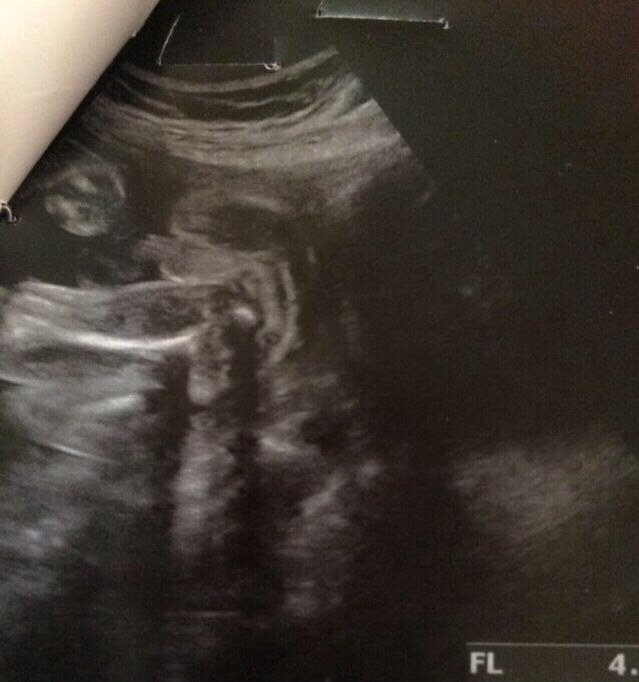

بما انه تجمع لاانجاب البنات اسال الله لكم تحقيق ماتتمنونه ويرزقني مااتمنى قلت ادخل التجمع واسالكم عن اشعة سونار بما انكم لديكم اولاد قبل ابي منكم هل الجنس ذكر في السونار ع كلام الدكتوره

وهذي الصور

سبحان الله واضح أنه ولد ربي يرزقك شوفته سليم ومعافي.